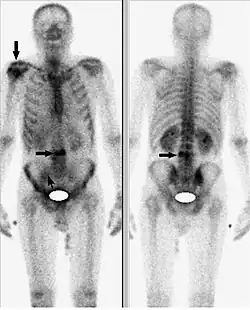

Исследование начинается с внутривенного введения 99mTc-золедроновая кислота (Резоскан) с активностью 5 МБк/кг с последующим сканированием спустя 1-3 часа после инъекции, с обязательным предварительным опорожнением мочевого пузыря. Равномерное поглощение вещества костями обычно говорит о норме. Фокальное поглощение (локальное поглощение, отличающееся по интенсивности от такового в соседней кости) может свидетельствовать об аномалиях. Если фокальное поглощение интенсивнее, чем поглощение в соседней кости, это может быть признаком артрита, перелома или наличия метастазов. Менее интенсивное, чем в соседних костях, фокальное поглощение указывает на возможный некроз опухоли, лизис новообразования или последствия лучевой терапии. Размеры ни одной из коммерчески доступных гамма-камер не позволяют получить изображение всего тела взрослого человека без перемещения камеры или пациента. Таким образом, сканирование скелета проводится с помощью перемещения камеры вдоль длинной оси пациента или перемещения пациента вдоль камеры. Для сканирования скелета детекторы размещают в положениях 90° и 270°, пациент лежит на спине ногами по направлению к гентри. Затем стол вместе с пациентом перемещается в точку начала сканирования, в которой голова пациента находится в поле зрения камеры. Во время исследования пациент и стол перемещаются таким образом, что сканирование идёт с головы до ног. Получение изображений всего тела («whole body»), которые представляют собой относительные значения поглощения радиомаркера в области головы, груди, брюшной полости и ног, требует точного кодирования и сопоставления параметров сканирования и движения пациента. Большинство таких процедур проводится с помощью гамма-камер, содержащих по два детектора, так что передняя и задняя проекции снимаются одновременно.

Наиболее значимым критерием проведения остеосцинтиграфии с помощью 99mTc-золедроновая кислота (Резоскан) является поиск метастатических поражений скелета. Качество проводимого исследования, главным образом, зависит от носителя и его тропности к костной ткани. Как уже отмечалось выше, в настоящее время, применяют дифосфонаты, где золедроновая кислота является максимально чувствительной к очагам повышенной резорбции кости.